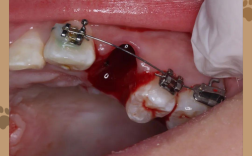

重度增生

- 临床表现:牙龈显著增生,覆盖牙面超过1/2甚至全部牙冠,质地坚韧或纤维化,呈暗红色或苍白色,易出血,伴发明显口臭、疼痛,严重影响咬合和口腔清洁,可能阻碍牙齿移动,延长正畸时间。

- 图片特征:牙龈组织弥漫性肿大,表面呈结节状或分叶状,与牙齿粘连紧密,部分区域可见溃疡或坏死(图片中可见牙龈增生明显,牙齿几乎被“包裹”,牙龈边缘肥厚,质地粗糙,颜色暗红)。